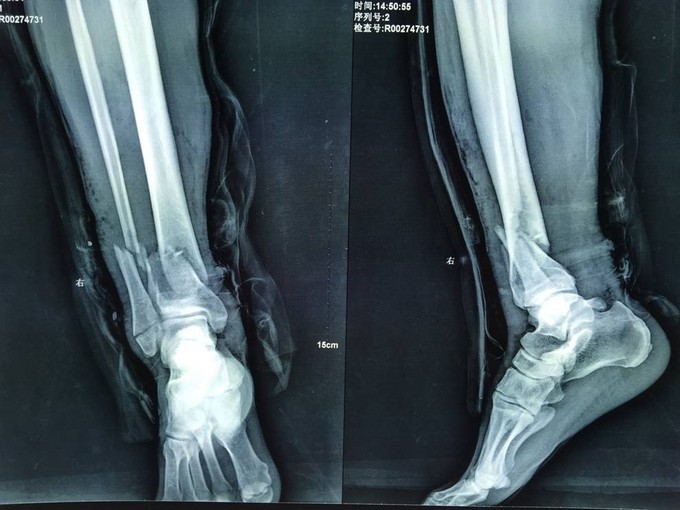

患者于2015年3月9日15时车撞伤后自觉左踝部一过性剧烈疼痛,意识清醒,行走障碍。急诊送至宽甸县医院,行DR及相关查体后提示:左胫腓骨远端开放骨折,行抗炎消肿止疼等对症治疗,现患者为求进一步治疗送至我院急诊,急诊以“左胫腓骨远端开放骨折”为诊断收入我科。患者病来,意识清楚,无咳嗽咳痰,无心慌气短,饮食正常,小便未排,大便未排,体重无变化。

左踝部肿胀,内踝可见大面积张力性水泡结痂,内踝尖部可见一开放口,内外踝处压痛阳性,左胫骨远端可触及骨擦感及骨擦音。双下肢感觉正常,双侧足背动脉搏动良好,末梢血运好。

诊断:左胫腓骨远端开放性粉碎性骨折 患者车祸入院后行行抗炎消肿止疼等对症治疗后约一周,局部皮肤软组织条件差,局部皮肤全层坏死,行左胫腓骨远端外固定架固定术。